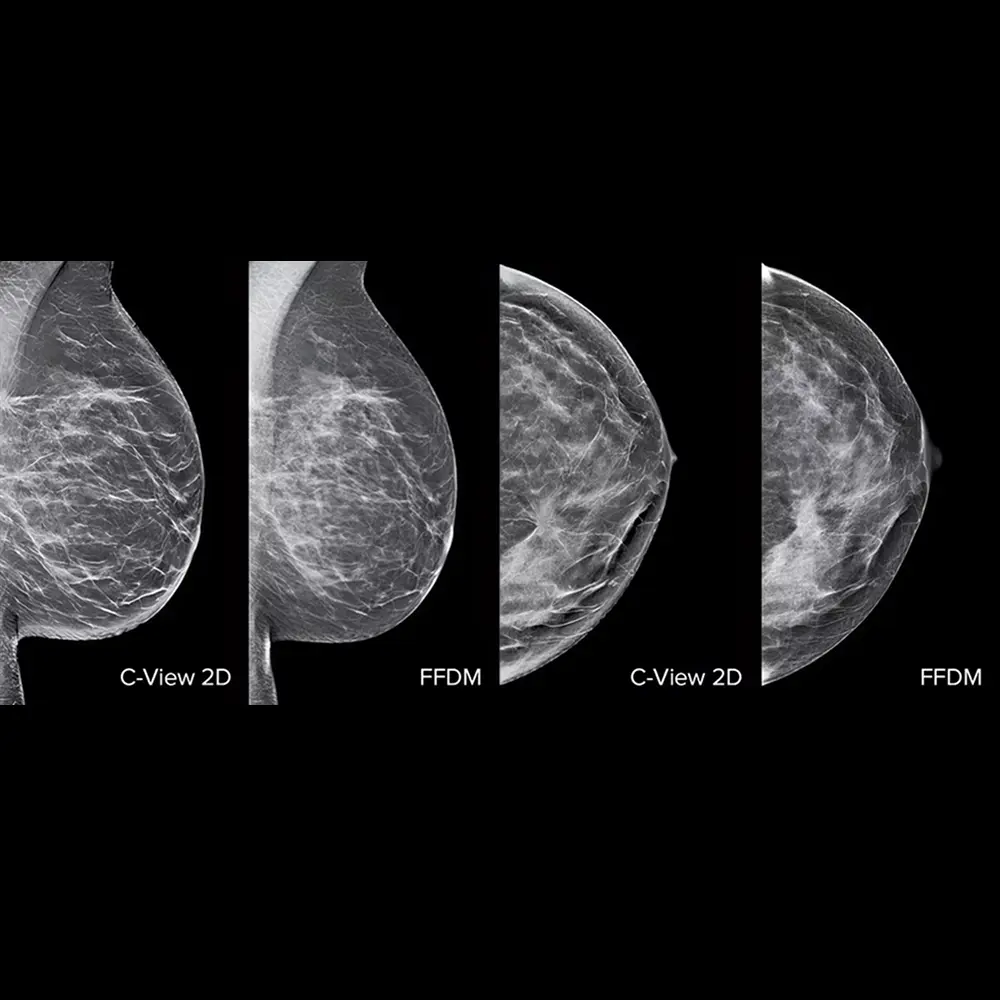

La tecnologia di imaging C-View rappresenta un’innovazione nell’ambito della mammografia digitale, permettendo ai radiologi di rilevare in modo rapido e accurato anche i più piccoli dettagli e la morfologia delle lesioni.

C-View elabora le immagini 2D sintetiche direttamente dai dati acquisiti durante la tomosintesi 3D, evitando l’esposizione aggiuntiva necessaria per le immagini 2D convenzionali. Questo approccio consente un esame a bassa dose, mantenendo la qualità diagnostica.

- Miglior visibilità di dettagli che potrebbero sfuggire alle immagini 2D tradizionali.

- Le immagini 2D generate da C-View sono utilizzate insieme agli strati tomosintetici per un’interpretazione completa e accurata dell’esame.